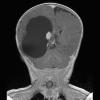

NEOPLASMS (NON-GLIAL NON-NEURONAL)

Choroid plexus papilloma (7)